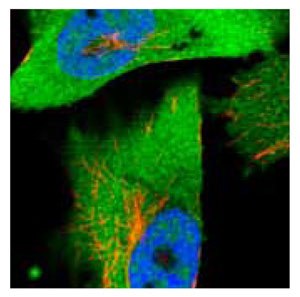

Anti-ACLY.Product No. HPA022959: Immunofluorescent staining of human cell line U-251MG shows positivity in nucleus but not nucleoli and cytoplasm.